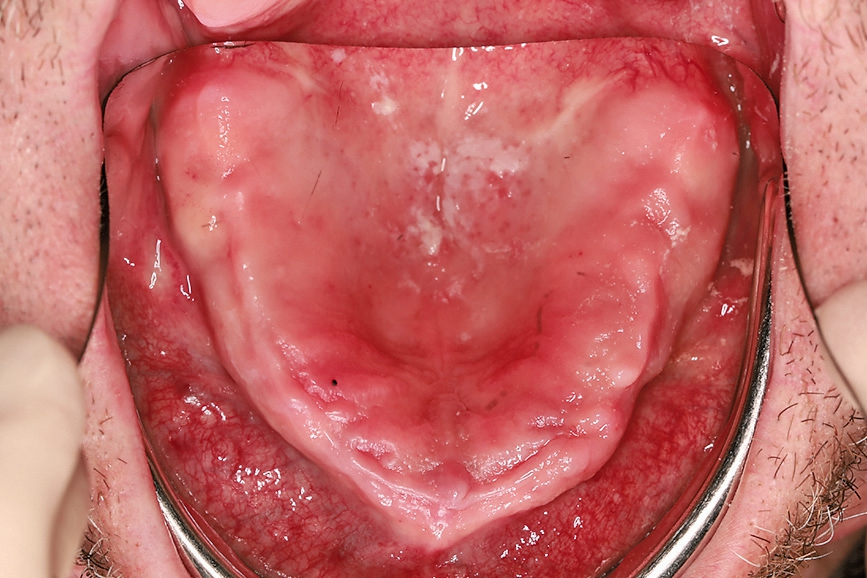

Der 49-jährige Patient trägt im Oberkiefer eine Prothese. Die Prothese im Unterkiefer hat ihn immer gestört, weswegen er diese schon länger nicht mehr getragen hat. Die Abbildungen 1 bis 3 zeigen den Ausgangsbefund. Während der Oberkiefer klinisch noch gut für Implantate geeignet erscheint, können im Unterkiefer schon Zweifel aufkommen. Bei genauerer Betrachtung des Oberkiefers in der Schichtaufnahme (OPG) kommt jedoch die Vermutung auf, dass der Knochen dünn sein könnte. Das war der Grund, warum wir vor der Implantation ein DVT erstellt haben.

Die Abbildungen 1 bis 3 zeigen die Ausgangssituation. Zuerst wurde nach der Herstellung einer Prothese eine Implantatplanung gemacht. In den Abbildungen 5 bis 7 zeigt sich die Herausforderung in diesem Fall: Geringe Platzverhältnisse für die Implantate im Knochen. Nachdem die erstellten Daten verschickt wurden, bekommen wir die Schablonen zurück (Abb. 8).